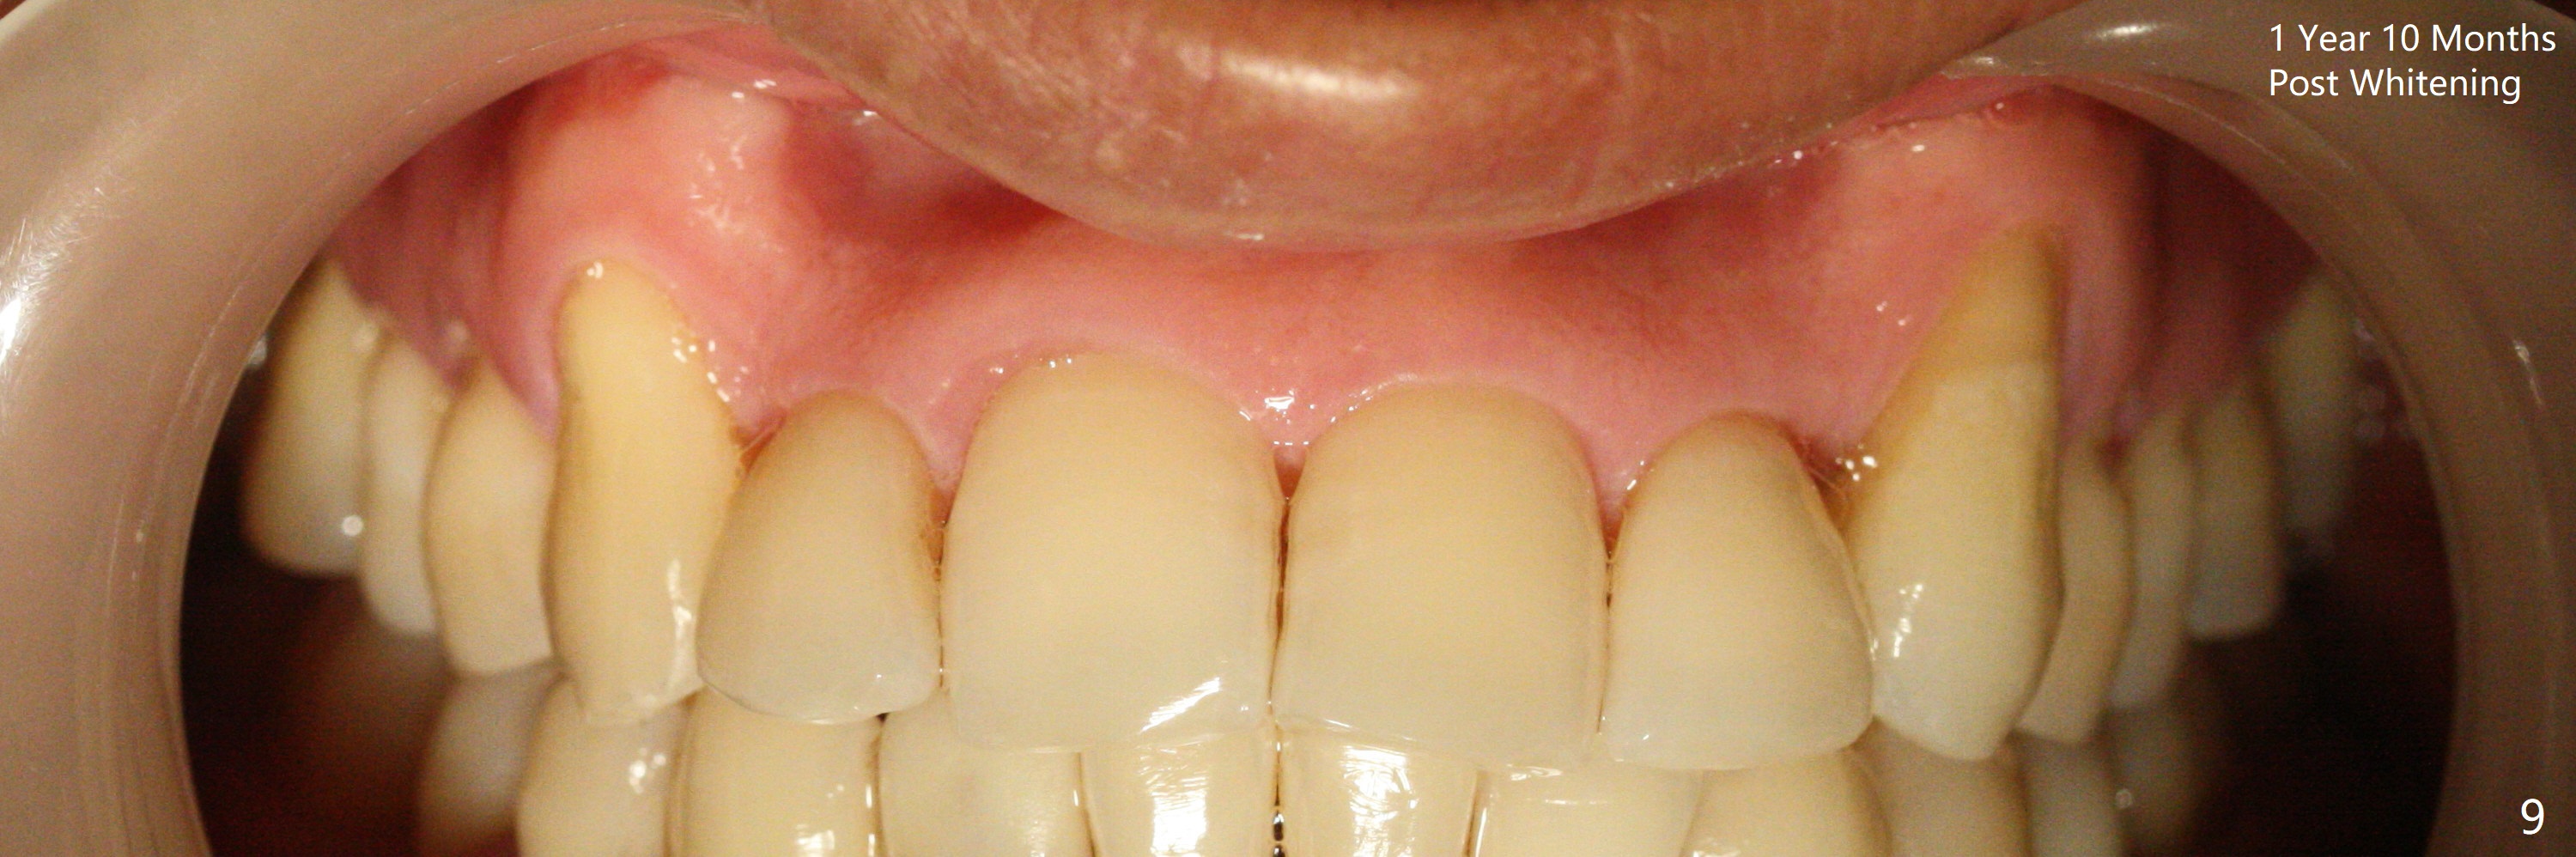

A 45-year-old man had severe malocclusion and chose non-extraction orthodontic treatment (Fig.1 (2012)). Five years later, the tooth #11 discolors (Fig.3, as compared to #6 in Fig.2). Immediately after RCT (Fig.4,5), the affected tooth has sudden change in shade (Fig.6). Two weeks later there is rebound in shade (Fig.7). The latter improves after two rounds of chair-side internal bleaching with 35% Hydrogen Peroxide for 20 minutes and build-up with the lightest shade composite (Fig.8). For optimum, place the bleach gel in the pulpal chamber and close the access with Cavit for a few days. In fact the latter is unnecessary. The treated tooth looks as normal as the tooth on the other side 1 year 10 months post whitening (Fig.9). PARL reduces 3 years post RCT (Fig.10 <, as compared to Fig.5).